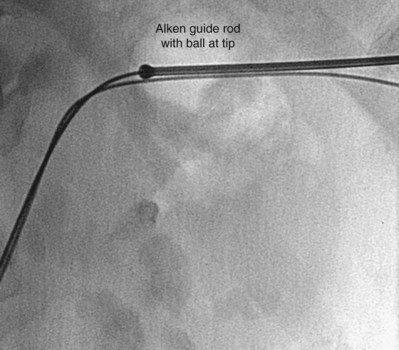

Rigid metal dilators, introduced by Alken (1985), are a series of progressively enlarging coaxial stainless steel rods that pass over an 8-Fr guide rod. The first step in tract dilation is to pass the 8-Fr guide rod over a 0.035-inch guidewire. The end of the guide rod has a ball that prevents advancement of the first dilating rod beyond the tip. The ball is positioned at the intended depth of the dilation (Fig. 47–23). After passing the first rod, each successive metal rod is passed sequentially over the former until the desired tract is achieved, up to a 30-Fr rod over which is passed a 30/34-Fr plastic sheath. The advantages of the rigid metal dilator system are that it is the most effective dilator, able to dilate even when there is dense perirenal scarring from prior procedures, and that is it inexpensive on a per-case basis because it is reusable. The disadvantage is that, for the same reason they are so effective, the rigid metal dilators can do considerable damage. The depth of the dilation can be hard to maintain accurately, especially when pushing hard against tough scar tissue. One group has modified the rigid metal rods, tapering the ends and adding centimeter markings (Shen et al, 2007).

Figure 47–23 Alken guide rod is positioned with the ball at the tip of the rod positioned at the intended depth of the dilation.